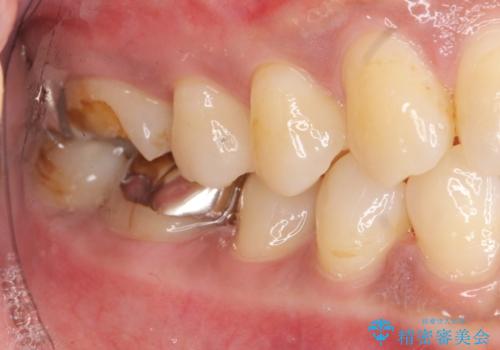

- 笑ったときに目立つ奥歯の銀歯を白くしたいという希望で来院されました。

銀歯を除去し、ジルコニアクラウンによる審美性の回復を計画します。